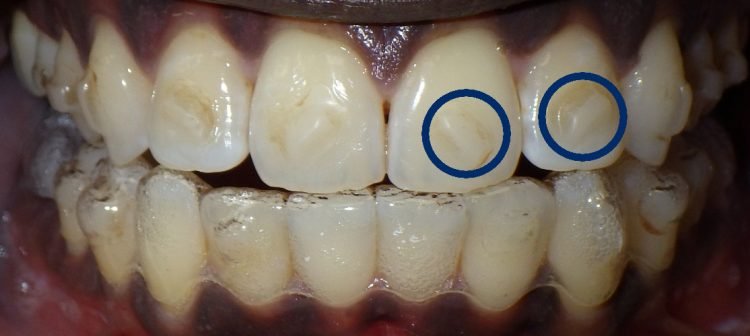

Clear aligner attachments are small, tooth-coloured bumps that are bonded to specific teeth before the clear aligners are placed. They are made of dental composite, and are designed to act as handles for the aligner to exert force on the teeth. This extra force helps to move the teeth more quickly and efficiently, and can also be used to correct more complex cases.

Clear aligner attachments are typically used in cases where the tooth movement required is more complex, or when additional force is needed to achieve the desired results. Some common situations where clear aligner attachments may be used include:

Attachments can be used to provide additional force to the teeth on either side of a gap, helping to close it more quickly.

Attachments can be used to provide extra force to rotate a tooth that is out of position.

Attachments can be used to provide additional force to level and align the bite, helping to correct open bites and crossbites.

Clear aligner attachments can be used to improve the overall aesthetics of a smile, by providing additional force to certain teeth that need to be moved.